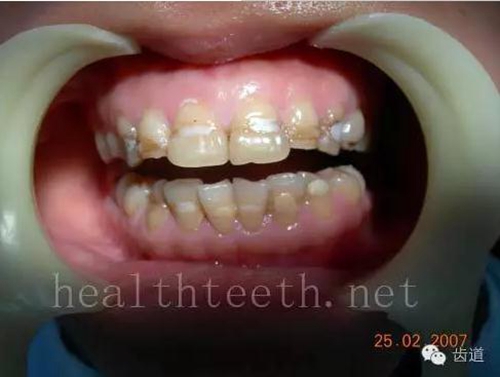

五、牙齒發(fā)育上的問題

變色牙

35.jpg

氟斑牙

36.jpg

釉質(zhì)發(fā)育不全

37.jpg

四環(huán)素牙

38.jpg

牙神經(jīng)治療后的牙齒變色

39.jpg

10歲孩子剛剛萌出的牙齒變色